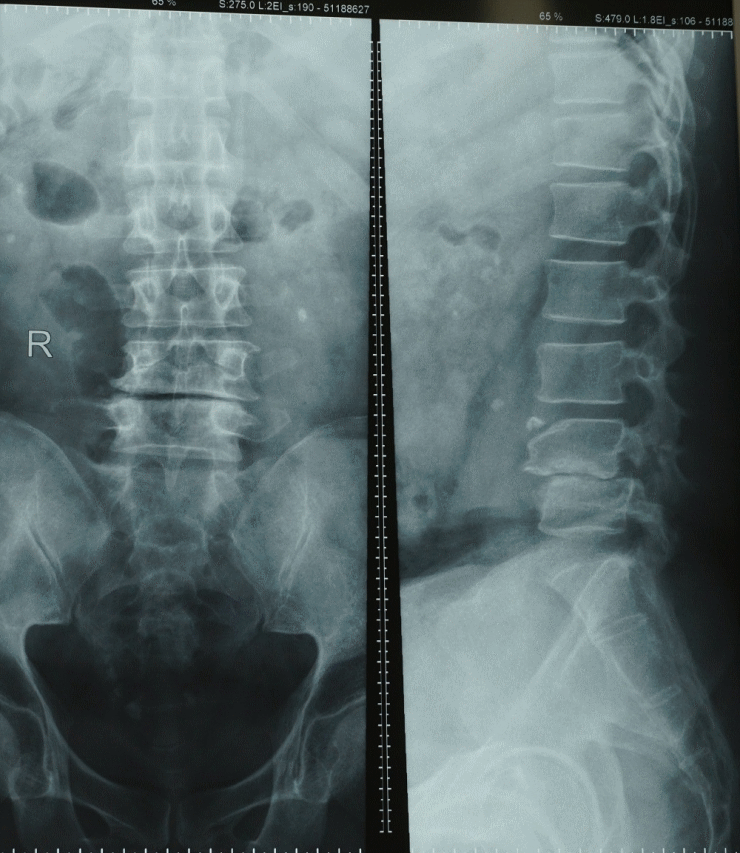

Khi có triệu chứng nghi ngờ thoái hóa cột sống, bác sĩ sẽ làm một số nghiệm pháp để xác định cơ lực, trương lực cơ và phản xạ đồng thời để xác định xem đã có biến chứng chèn ép thần kinh hay chưa. Sau đó, người bệnh sẽ được làm một số xét nghiệm hình ảnh như X-quang, MRI để chẩn đoán bệnh và xác định mức độ tổn thương. Một số trường hợp cần thiết có thể được làm điện cơ đồ (EMG) để chẩn đoán.